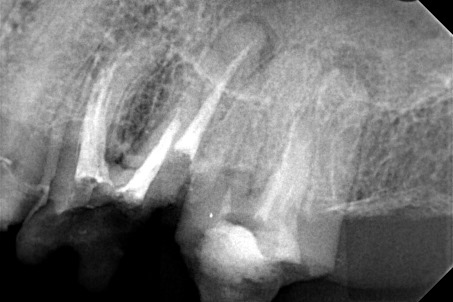

Ο ασθενής επιθυμούσε την προσθετική αποκατάσταση (με θήκη / στεφάνη δοντιού) του πρώτου γομφίου στην αριστερή πλευρά της κάτω γνάθου, καθώς το δόντι αυτό είχε ένα παλιό σφράγισμα το οποίο συνεχώς έσπαζε. Απαραίτητη προϋπόθεση για την έναρξη της διαδικασίας για τη στεφάνη δοντιού ήταν η κλινική και ακτινογραφική εξέταση του γομφίου. Μετά τη λήψη ακτινογραφίας αποκαλύφθηκε οτι το δόντι είχε μία παλιά απονεύρωση, η οποία ήταν ατελής εφόσον δεν εκτεινόταν σε όλο το μήκος των ριζικών σωλήνων του δοντιού ενώ φαινόταν ο τρίτος ριζικός σωλήνας στο δόντι να μην έχει εντοπιστεί. Μετά από συνεννόηση με τον ασθενή αποφασίστηκε η επανάληψη της απονεύρωσης του δοντιού, ώστε να εξασφαλιστεί ένα εγγυημένο προσθετικό αποτέλεσμα. Γενικότερα είναι επιθυμητό οι προσθετικές εργασίες να τοποθετούνται στα δόντια εφόσον έχουν γίνει όλες οι απαραίτητες εργασίες όπως απονεύρωση δοντιού, καθαρισμός των ούλων κ.α.

Μετά λοιπόν την αφαίρεση του παλιού σφραγίσματος εντοπίστηκε ο τρίτος ριζικός σωλήνας που δεν είχε βρεθεί στην παλιά πρώτη απονεύρωση, όπως δείχνει και η φωτογραφία της αρχικής κλινικής εικόνας. Στη συνέχεια καθαρίστηκαν και επεξεργάστηκαν όλοι οι ριζικοί σωλήνες (Για περισσότερες πληροφορίες Βλέπε Επανάληψη απονεύρωσης). Η διαδικασία ολοκληρώθηκε με την έμφραξη των ριζικών σωλήνων του δοντιού και την ανασύσταση της εκτεταμένης κοιλότητας με ειδικό άξονα υαλονημάτων και ρητίνη. Ακολούθως το δόντι τροχίστηκε, λήφθηκαν αποτυπώματα και όταν ο οδοντοτεχνίτης είχε έτοιμη τη θήκη του δοντιού αυτή κολλήθηκε στο δόντι.